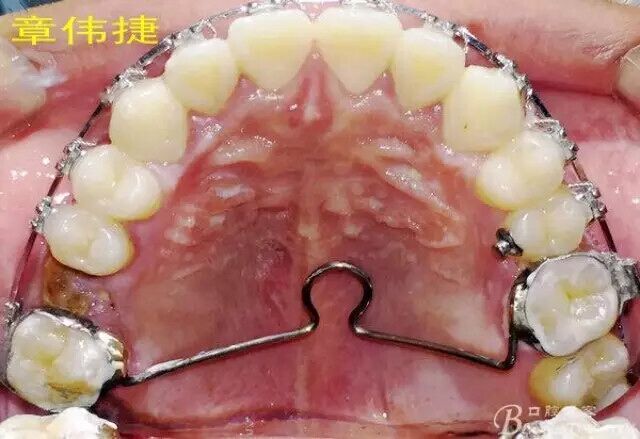

術(shù)前資料: